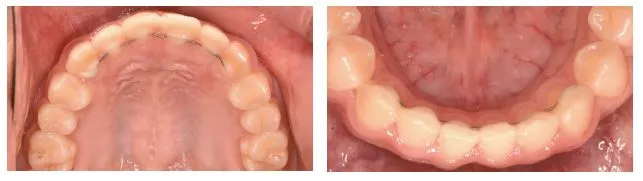

가지런한 치아배열과 좋은 교합관계를 유지하기 위해 교정치료 후 ‘유지장치’를 사용하게 된다. 일반적으로 널리 사용되는 장치는 앞니의 안쪽에 부착하는 ‘고정식 유지장치’와 환자가 탈착할 수 있는 ‘가철식 유지장치’이다. 이와 같은 유지장치는 환자가 가졌던 부정교합 및 환자의 치료 후 상태에 따라 적절히 디자인하여 제작된다.

96호 병원보 20.JPG 그림1. 고정식 유지장치

교정치료를 종료한 직후 앞니의 치아 배열은 특히 흐트러지기 쉬우며 이를 방지하기 위해 교정치료를 종료하

기 전 또는 직후에 얇은 철사를 앞니의 안쪽에 부착하게 되는데 이것이 고정식 유지장치이다 (그림 1). 일반적인 교정장치와 달리 치아의 안쪽에 장치가 부착되므로 겉으로는 잘 보이지 않는다.

96호 병원보 21.JPG 그림2. 일반적인 가철식 유지장치

가철식 유지장치는 고정식 유지장치와 달리 환자가 원할 때 착탈이 가능한 장치로 (그림 2), 교정치료 종료 후

보통 3개월 정도는 식사 및 양치할 때를 제외하고 자는 시간도 포함하여 거의 하루 종일 사용하게 된다. 이후에는 환자의 상태에 따라 밤에 잘 때 착용하는 등 사용 시간을 줄일 수 있다. 일반적인 가철식 유지장치는 치

과용 플라스틱 재료와 철사로 이루어져 있어 장치를 착용하고 있는 것을 다른 사람이 쉽게 알 수 있다 (그림 2).

96호 병원보 22.JPG 그림3. 투명 가철식 유지장치

심미적으로 문제가 된다면 경우에 따라 투명 가철식 유지장치를 선택할 수도 있다 (그림 3). 다만 투명 유지장치는 장기간 사용 시 착색 및 변색이 되어 보기에 좋지 않게 되고 깨지거나 구멍이 나는 등 내구성이 떨어져 수개월에 한번 재제작이 필요할 수 있다는 단점이 있다.